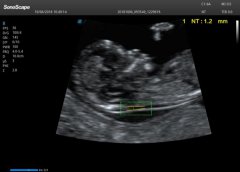

开立医疗:重视产检 避免“321”的遗憾

深圳 2020年3月23日 /美通社/ -- 321,对于大多数人来说可能只是几个普通的数字,但从2011年开始,世界卫生组织就赋予了这三个数字独特的含义:3条21号染色体,3月21日也成为了一个不平凡的日子 -- 世界唐氏综合征日。 开立...……